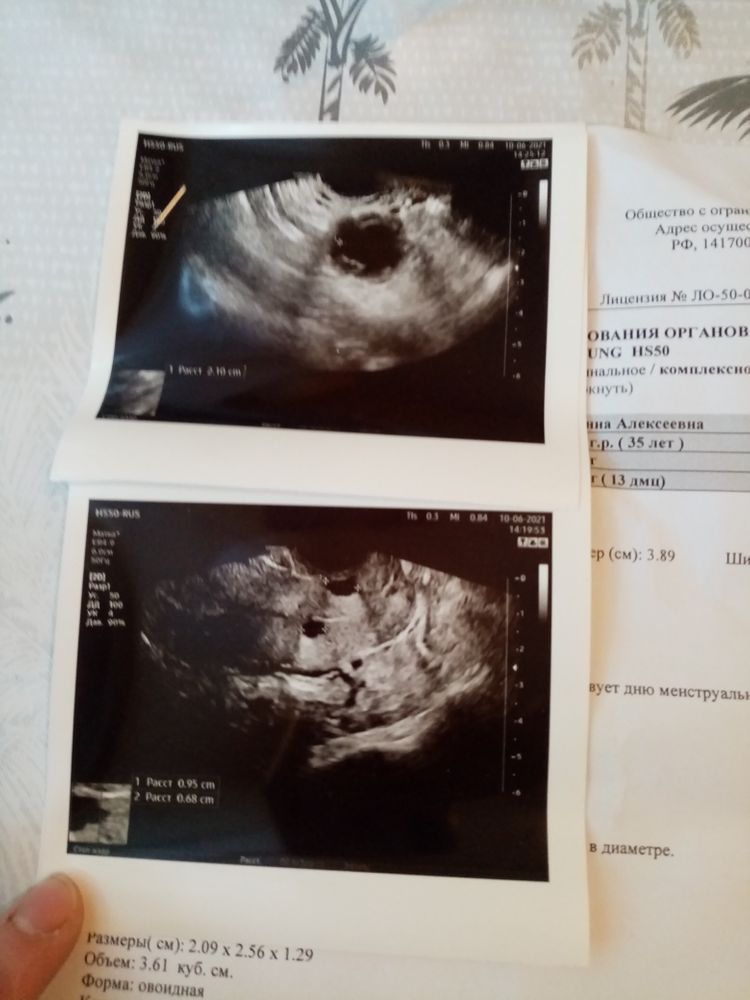

Вчера писала про ударную дозу укола хгч, так вот сегодня пошла на узи, получается 4 день после укола и мне сказали все лопнуло. Но вот когда О было, точно не сказала, сказало вот вот, возможно вчера. А можно по размерам ж. т узнать когда она была. Размер ж.т 21мм

Татьяна, Д.Ф был 20мм.Узистка сказала, что моё самолечение хорошо закончилась, что все там хорошо. И два раза повторила, что это точно не киста, а ж.т. Сказала что теперь только ждать и удачи пожелала

По жт трудно что то сказать. Вот про жидкость в пмп ничего не сказано, или я не увидела.. Да и какая разница когда была, ГЛАВНОЕ ЧТО БЫЛА!

Марина Сиреньщикова, про жидкость, она мне сказала что есть и даже показала. Я просто переживаю что секс был в день укола и через день, это вчера.